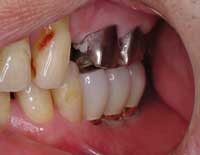

| Before | After |